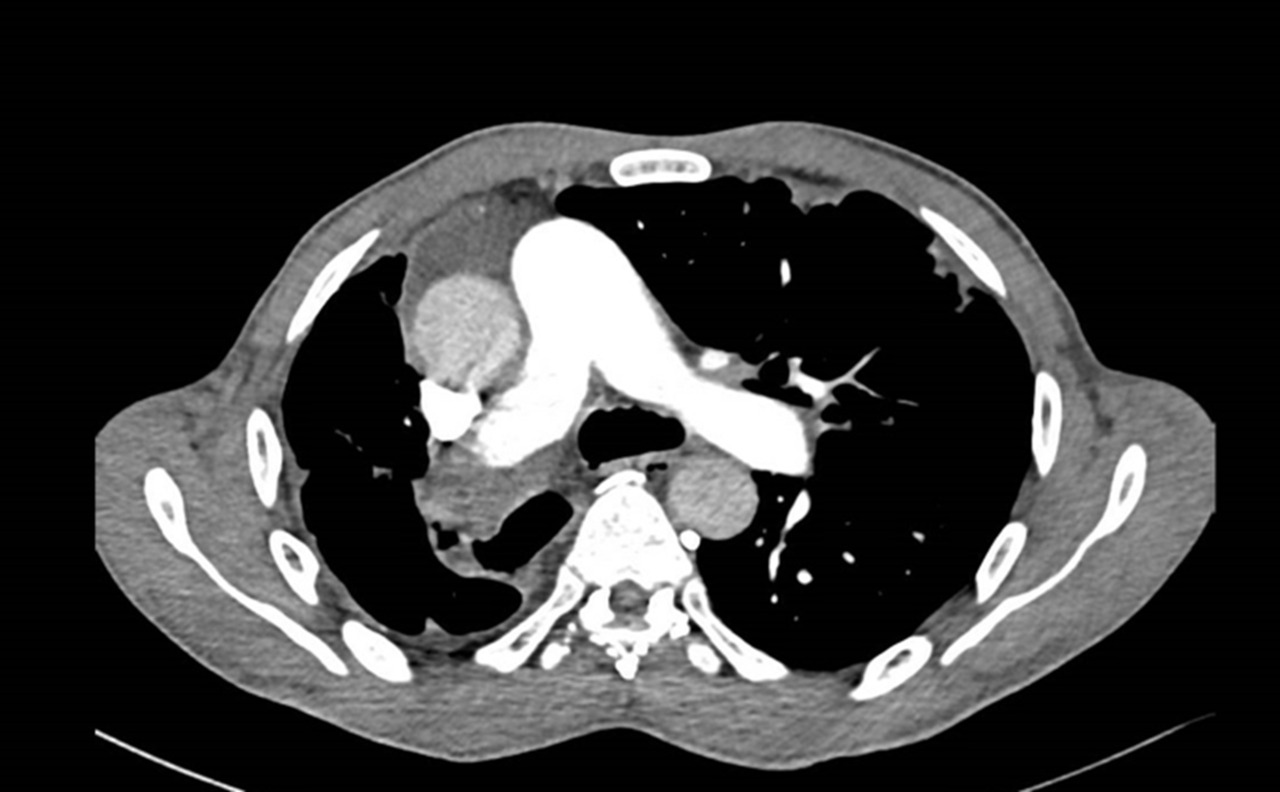

Vous êtes interne de garde aux urgences. Un patient de 71 ans est adressé par son médecin traitant pour dyspnée aiguë.

À l’arrivée, les constantes du patient sont : pression artérielle (PA) = 167/119 mmHg ; fréquence cardiaque (FC) = 114/min ; température (T) = 37,2 °C ; saturation en oxygène (SpO2) = 82 % en air ambiant ; fréquence respiratoire (FR) 30/min.